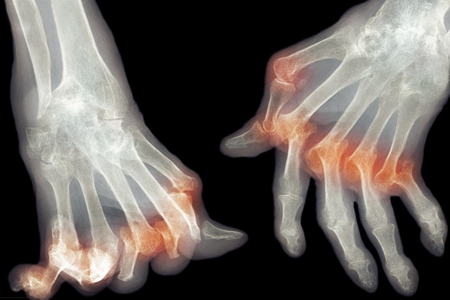

类风湿关节炎(RA)是一种病因未明的慢性、以炎性滑膜炎为主的系统性疾病。其特征是手、足小关节的多关节、对称性、侵袭性关节炎症,经常伴有关节外器官受累及血清类风湿因子阳性,可以导致关节畸形及功能丧失。